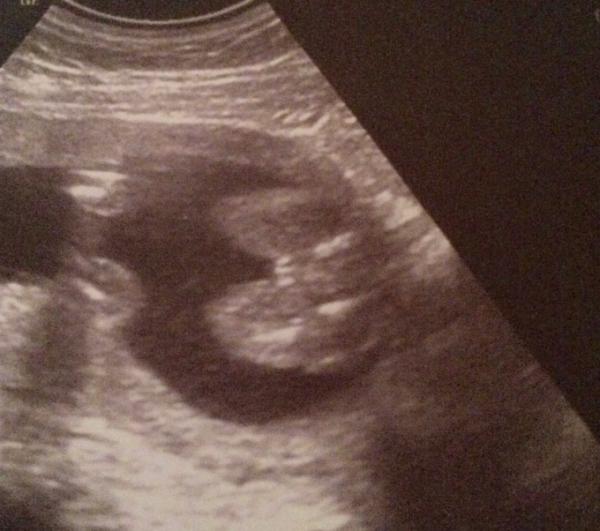

Hallo aus dem März bus hier unser Foto vom Mädchen outing

Bild zu